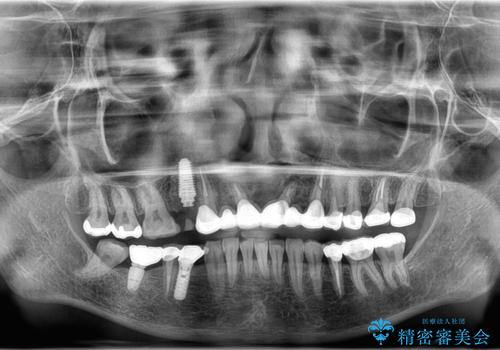

1日で抜歯、インプラント埋入、骨補填材を填入し仮歯【1DAYインプラント】までを数時間で行いました。

術後もほとんど痛みがなく経過も良好です。

3ヶ月後には、オールセラミック治療も終わり、短期間治療の為とても楽でしたと喜んでいただけました。